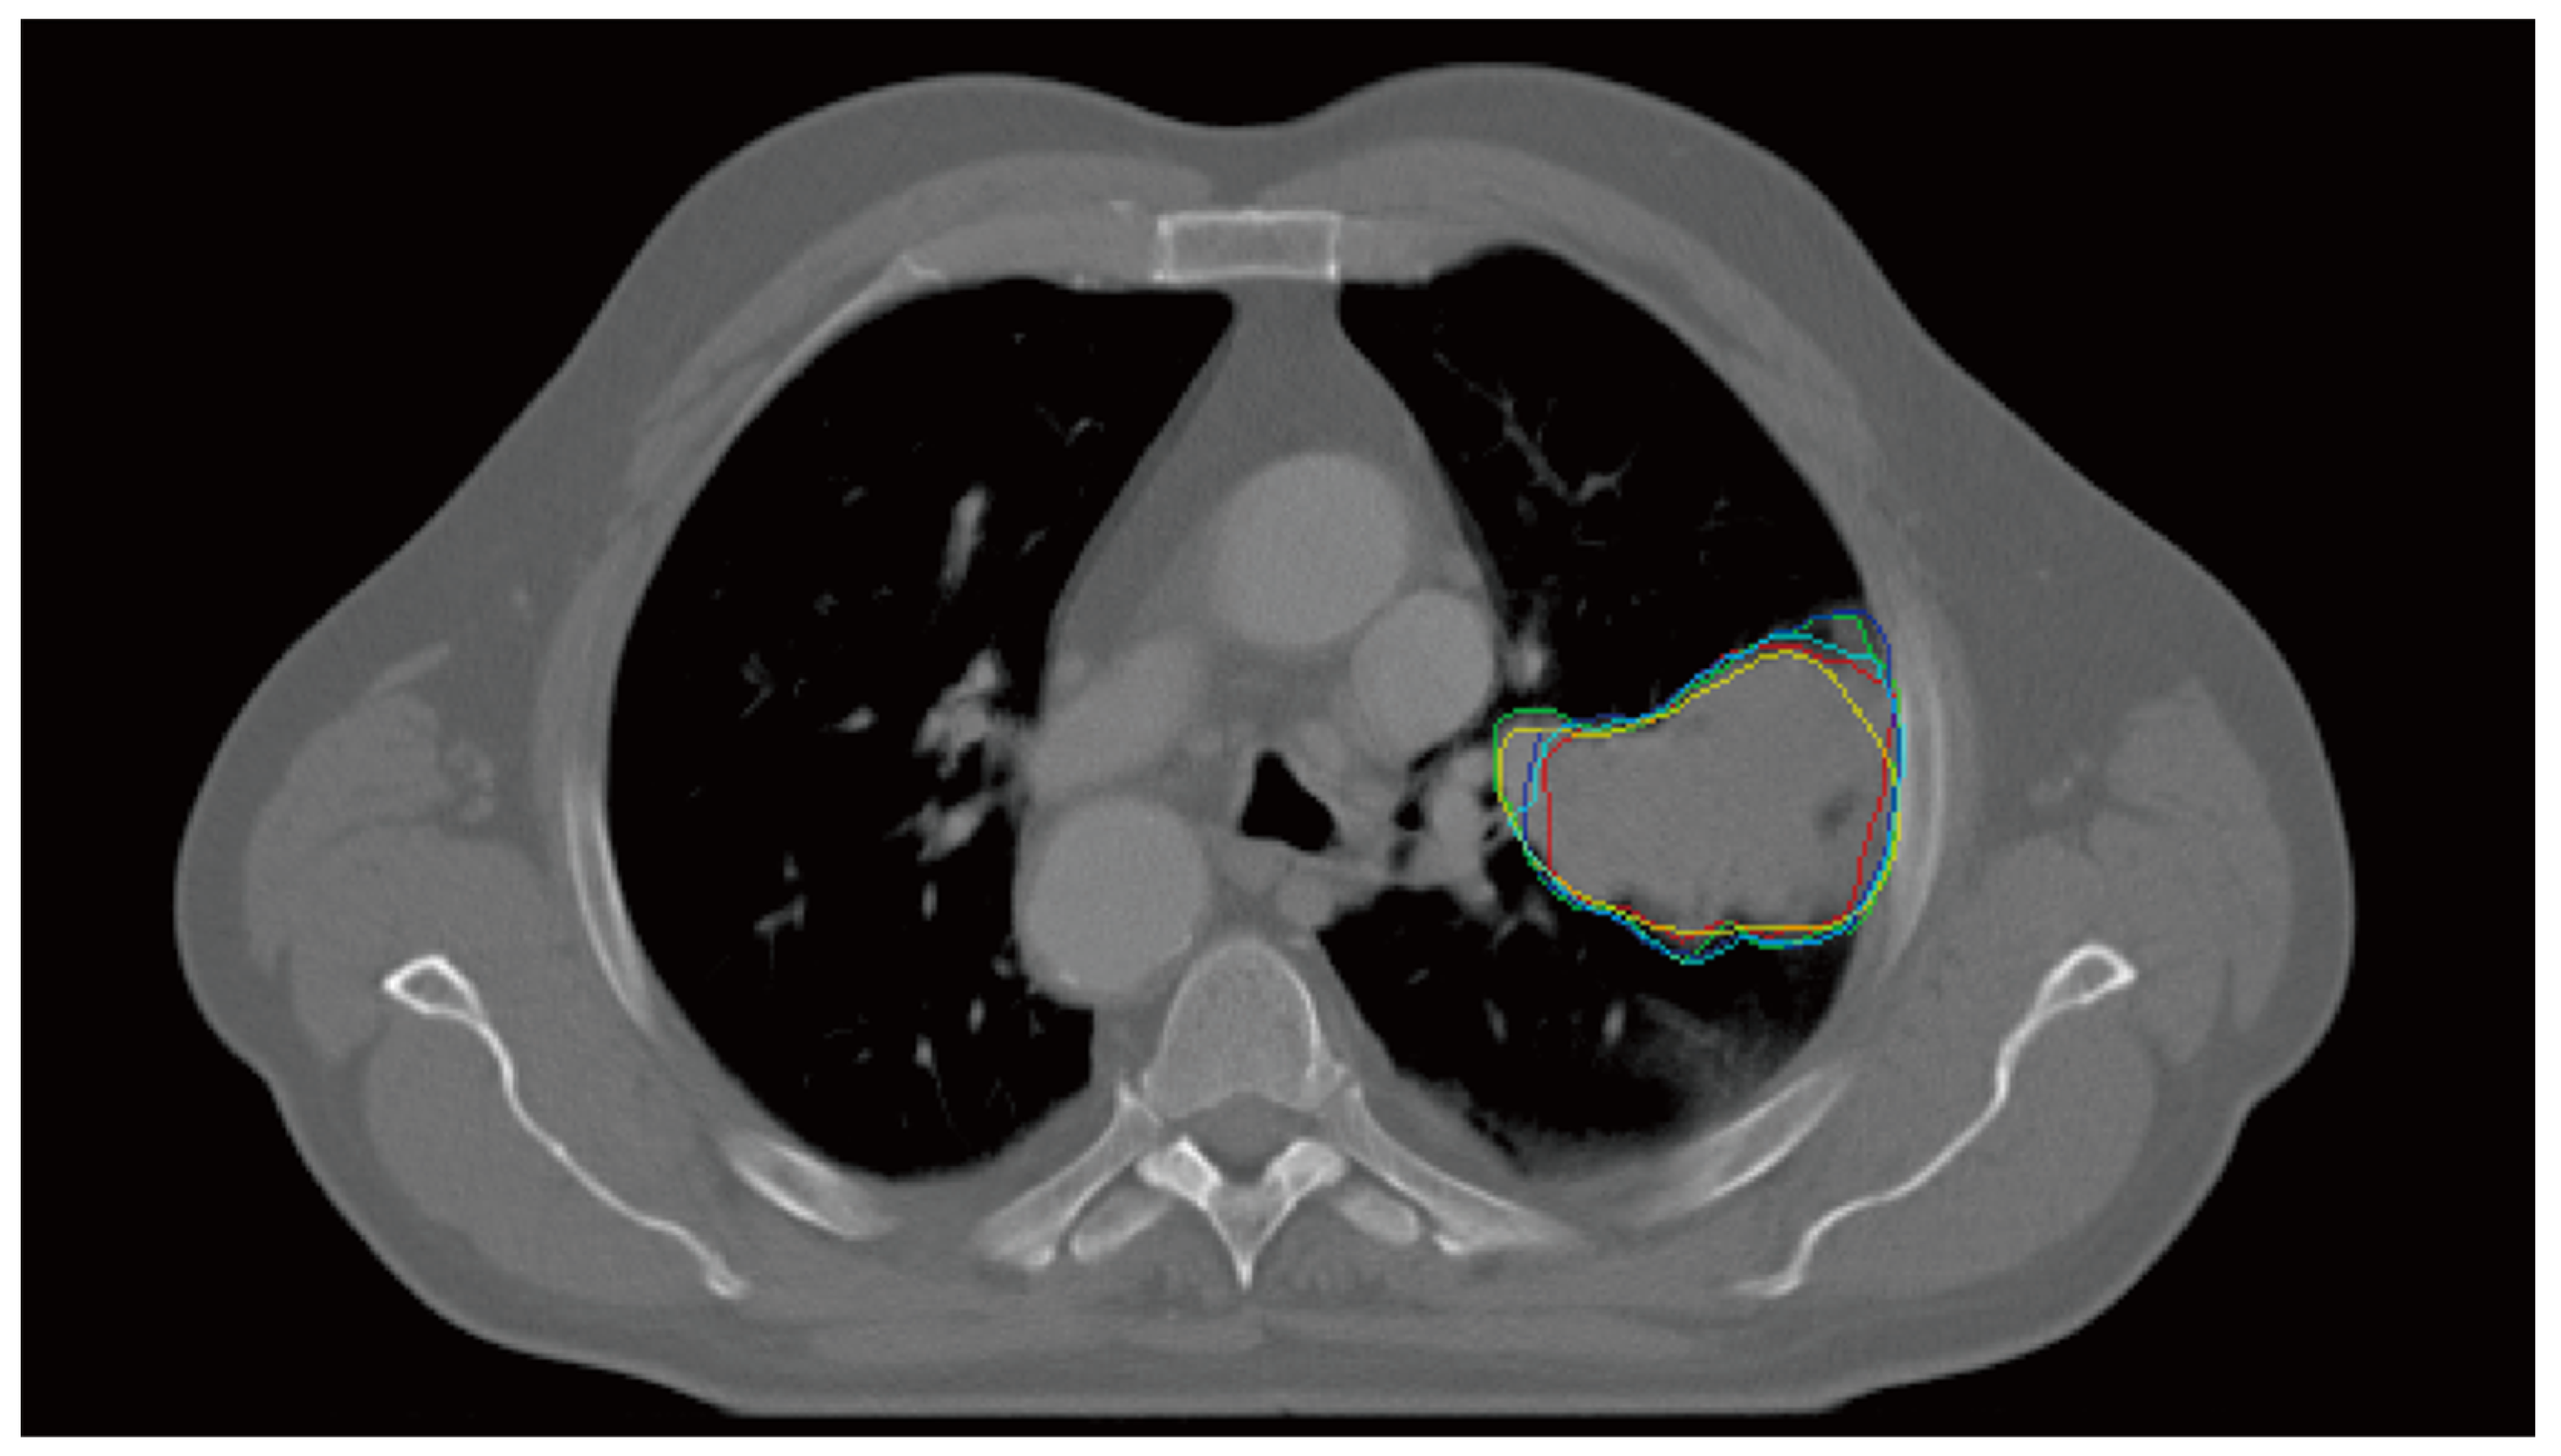

Interobserver Variability Prediction of Primary Gross Tumor in a Patient with Non-Small Cell Lung Cancer

2.1. Multiple Delineation Database

2.2. IOV Map: Ground Truth

2.3. IOV Prediction Model: IOV-Net